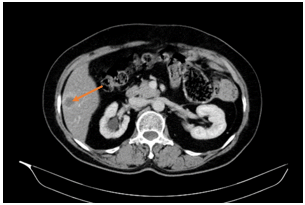

Ca lâm sàng: Điều trị đích bệnh nhân ung thư phổi không tế bào nhỏ giai đoạn muộn di căn nhiều cơ quan, tại Trung tâm Y học hạt nhân và Ung bướu – Bệnh viện Bạch Mai

Ung thư phổi là nguyên nhân hàng đầu gây tử vong do ung thư trên toàn thế giới. Trong đó, ung thư phổi không tế bào nhỏ (NSCLC) là thể thường gặp nhất, chiếm khoảng 85% các trường hợp [1]. Phần lớn bệnh nhân được chẩn đoán ở giai đoạn tiến...